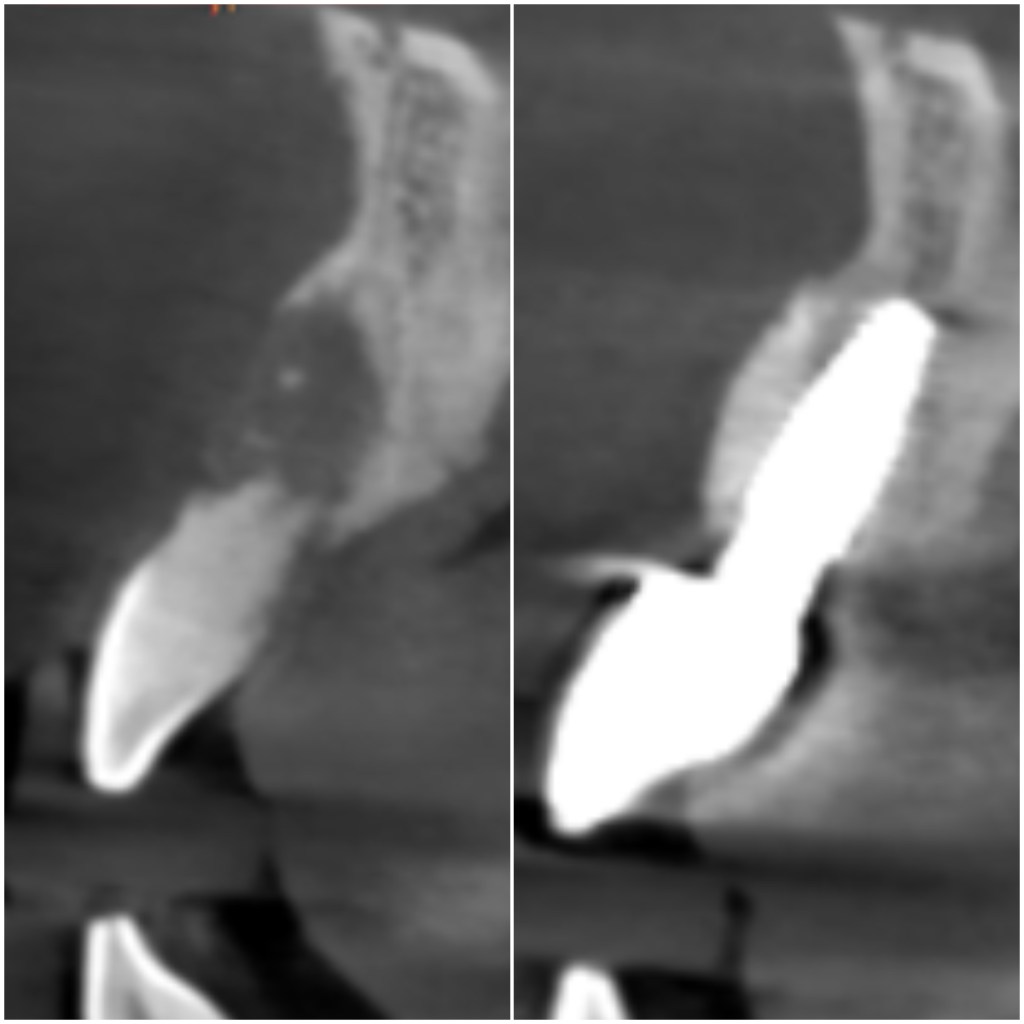

✔ 3D電腦斷層(CBCT)評估骨量